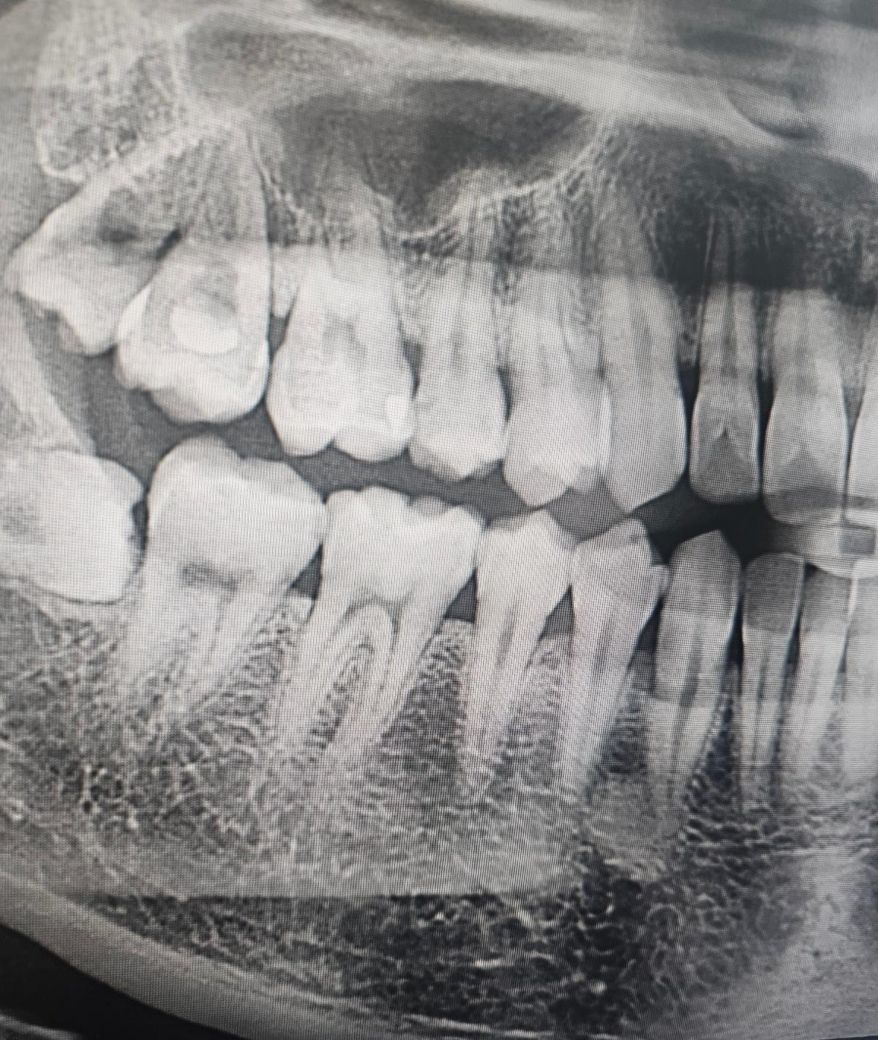

인접면충치 전문가분들의 의견이 궁금합니다

첫번째병원에선 즉 크라운7~8개를 하라고하셨는데 내이빨을 너무 많이 갈아내야 하는게 아닌가... 싶고

두번째병원에선 의사마다 견해와 처방이 다르다 이전병원은 충치인지 아닌지 약간만 의심되도 일단 갈아내고 없애야한다는 판단인거같다고 말씀하셨고 두번째병원에서는 인접면충치가 확인하기 힘들 뿐더러 갈아냈는데 충치가 아닐수도있다~ 라고 애매모호하게 말씀하셨어요

• 2번 째 사진